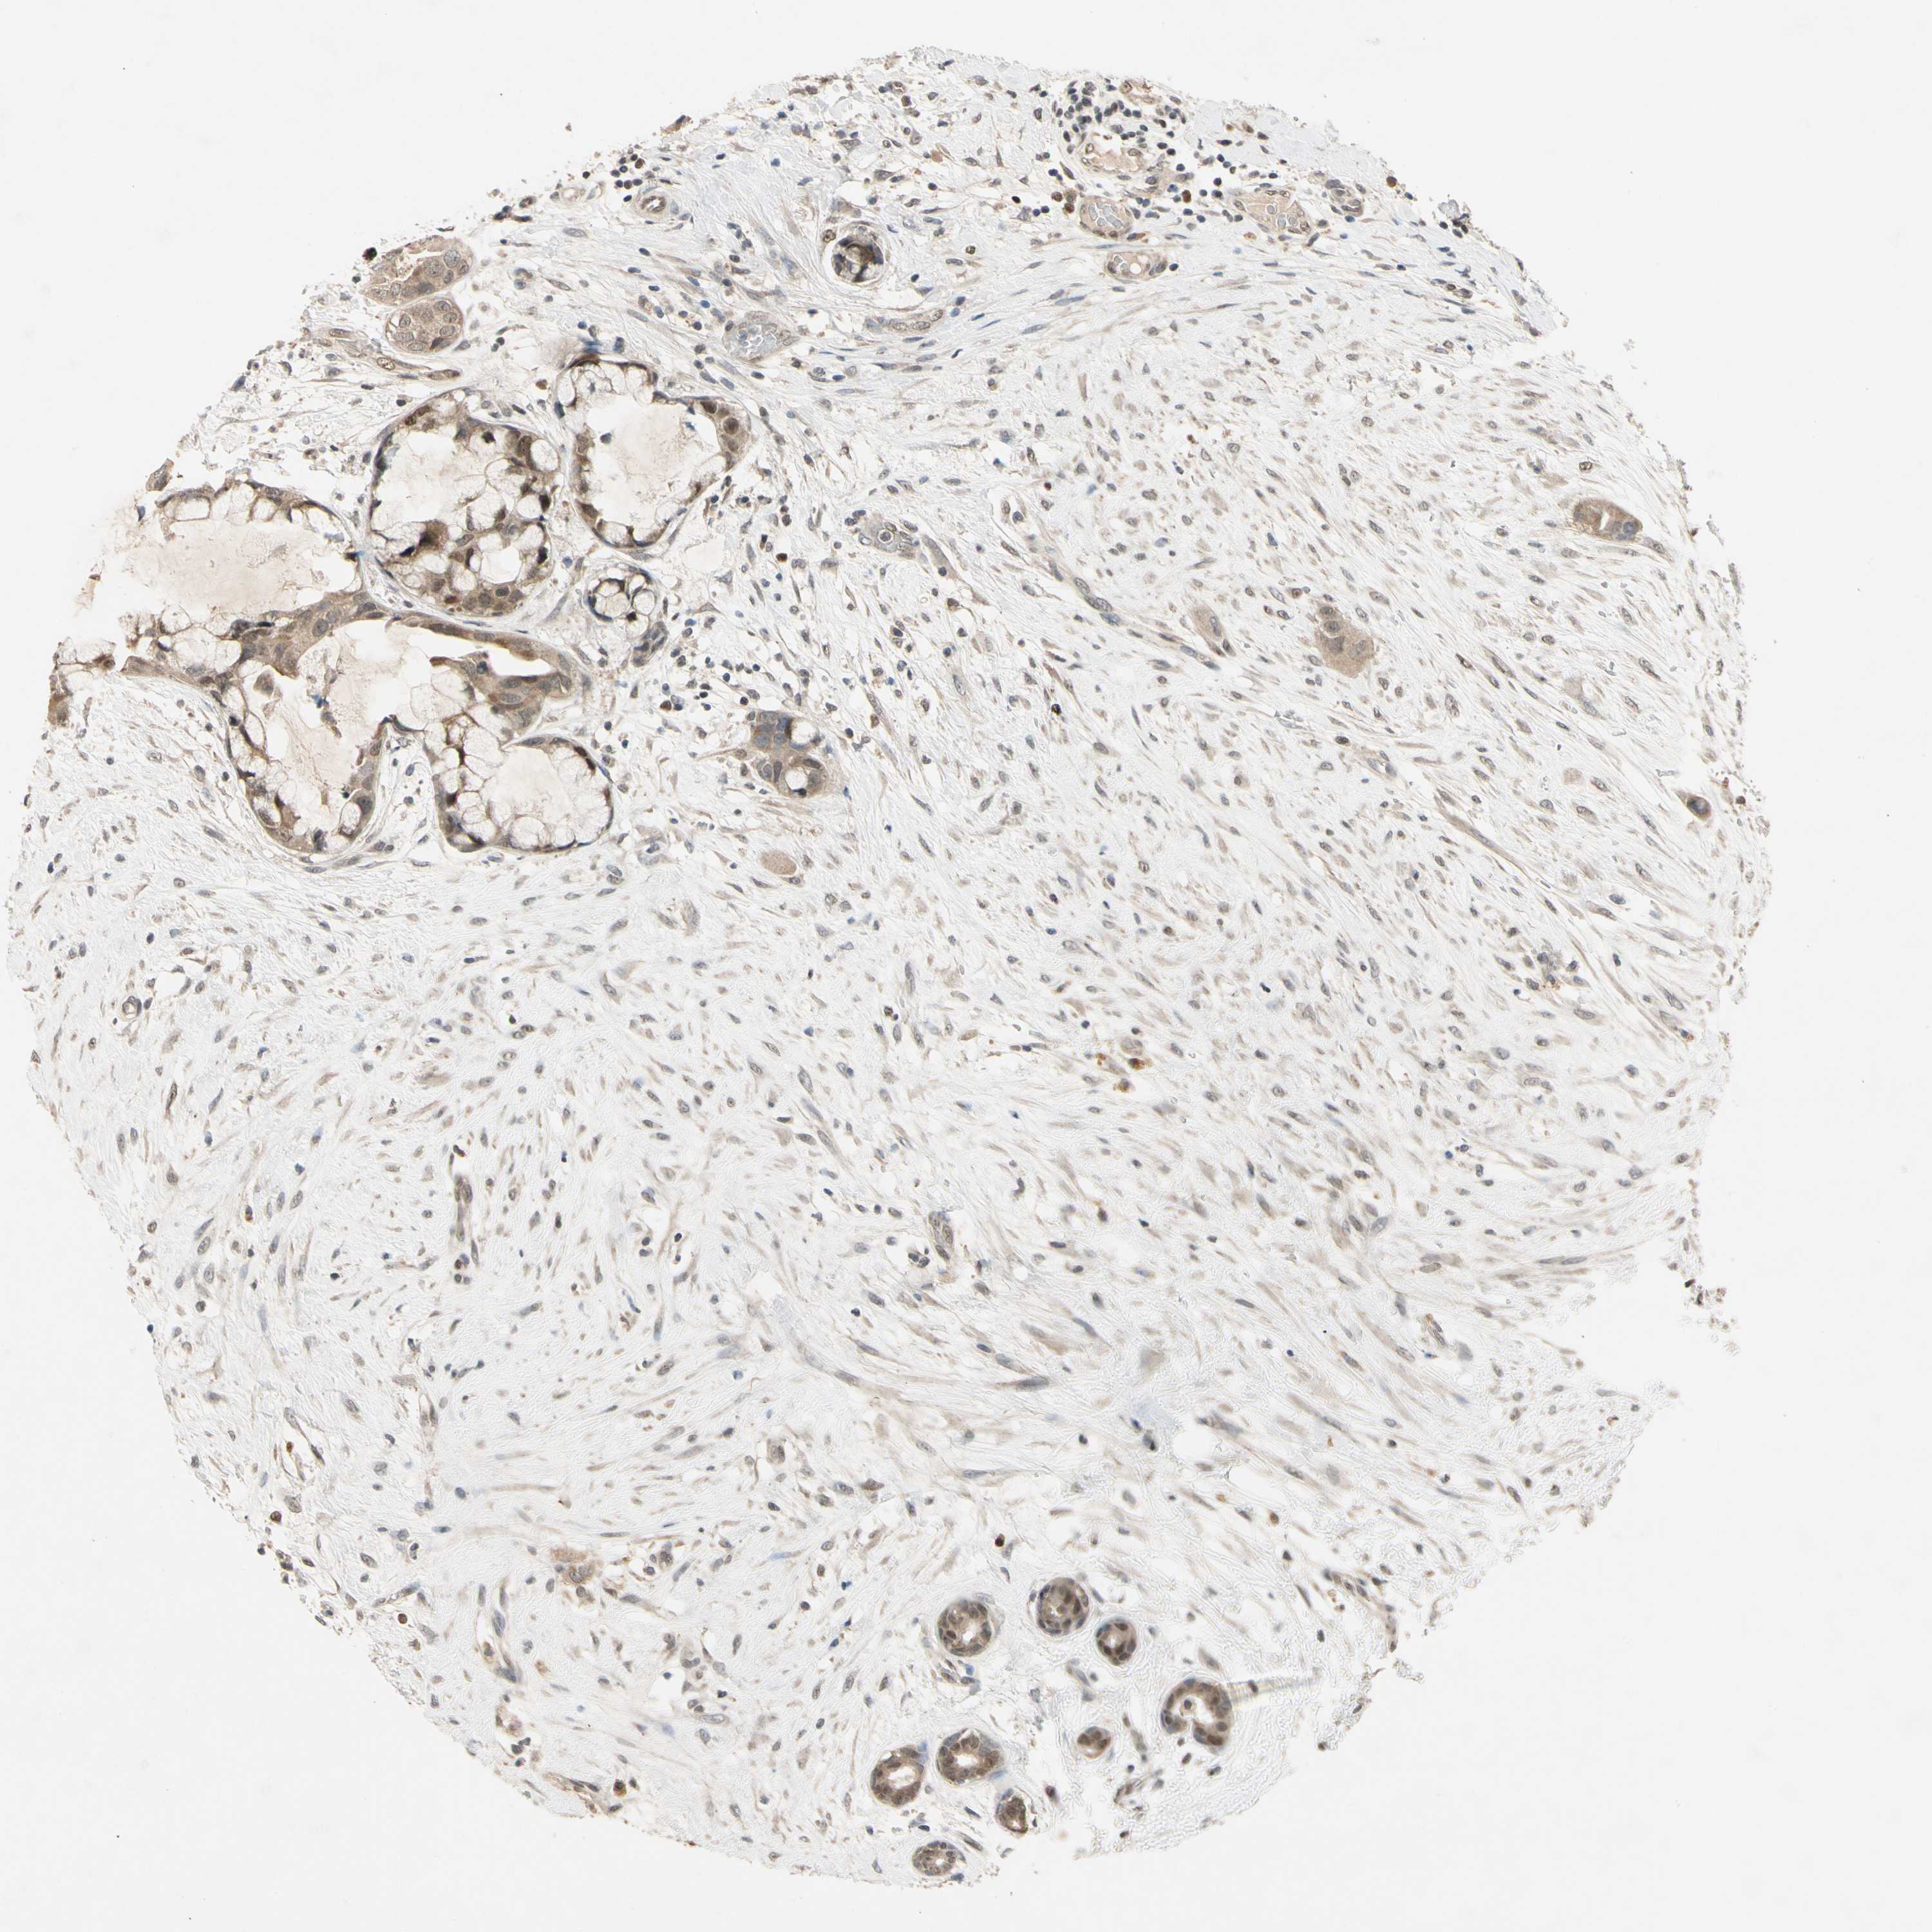

CANCER BREAST CANCER Show tissue menu

BRCA TCGA BRCA VALIDATION PROTEIN EXPRESSION

RIOX2 is potential prognostic, high expression is unfavorable in Breast Invasive Carcinoma (TCGA)